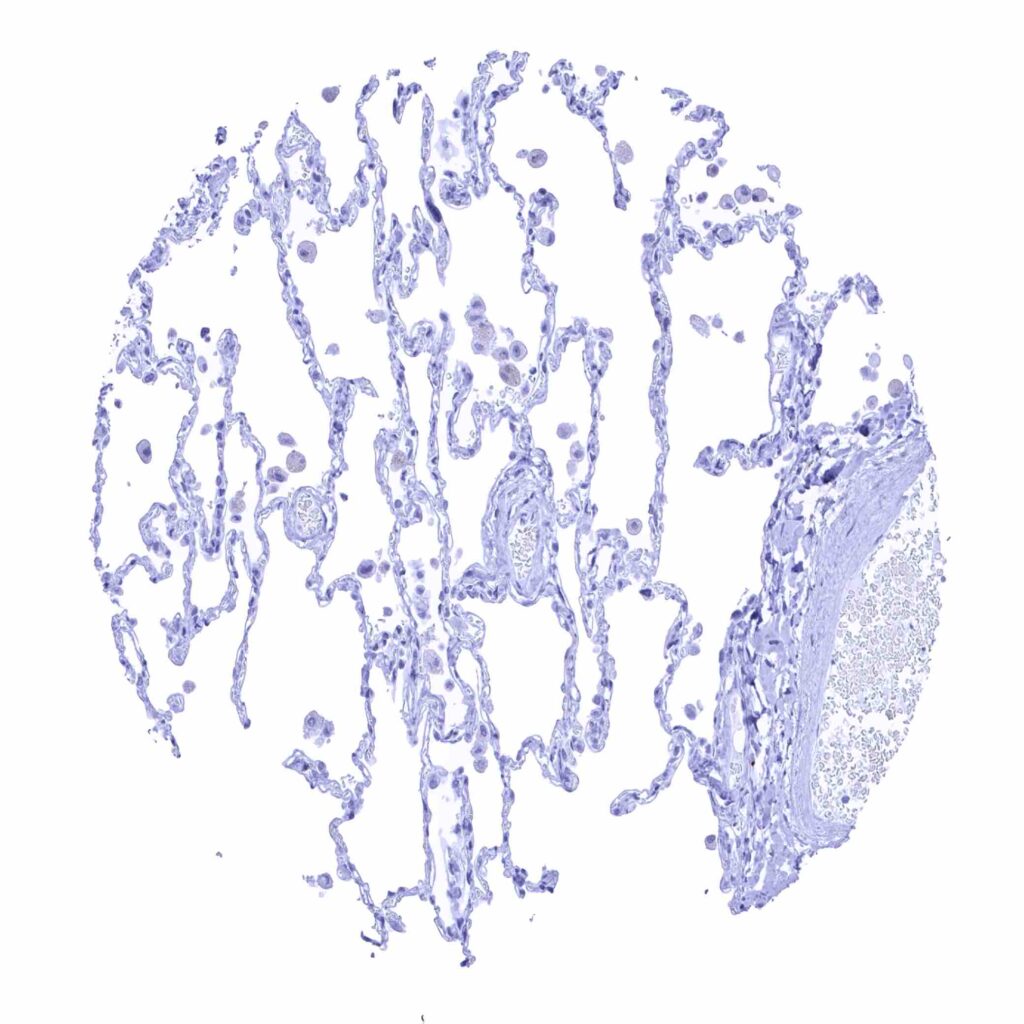

Lung

Lymph node